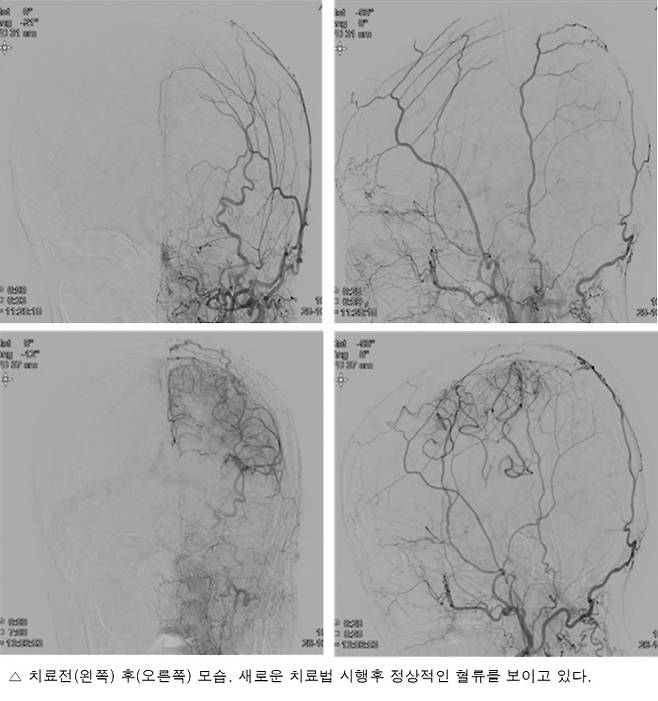

이러한 가운데 아주대병원 뇌졸중팀은 미국심장학회가 발행하는 세계 최고 권위의 학술지 'Stroke' 최신호(온라인)에 'Transdural Revascularization by Multiple Burrhole After Erythropoietin in Stroke Patients With Cerebral Hypoperfusion: A Randomized Controlled Trial(저관류성 뇌졸중 환자에서 에리스로포이에틴 약물 투여 후 두개골 구멍을 통한 경경막 혈관 재생 : 무작위 배정연구)'라는 제목으로 뚫을 수 없는 뇌경색 환자에서 새로운 혈관을 빠르게 생성해 감소한 혈류를 회복시키는 새로운 치료법을 발표했다고 29일 밝혔다.

뇌졸중팀(신경과 홍지만·이진수·이성준, 신경외과 임용철 교수)은 2016년 7월부터 2019년 7월까지 막힌 뇌혈관을 뚫기 힘든 급성기(증상발생 2주 이내) 혈관 폐쇄성 뇌졸중 환자 42명(모야모야병 11명, 만성 동맥경화성 혈관 폐쇄 31명)을 대상으로 이 새로운 치료법을 시행했다. 대상자는 부분마취로 구멍만 뚫은 환자군(21명)과 약물과 구멍을 뚫는 병합치료 환자군(21명) 2개 그룹으로 나눠 분석했다.

그 결과 반구혈관재형성은 구멍 단독군과 병합치료군이 각각 12명/21명(57.1%), 19명/21명(90.5%)에서 성공했으며, 혈관재형성 비율은 구멍 단독군이 총 58개 구멍 중 30개(51.7%) 구멍에서, 병합치료군은 총 58개 구멍 중 42개(72.4%) 구멍에서 혈관이 재생돼 병합치료군이 구멍 단독군에 비해 치료성적이 더 큰 것을 확인했다.